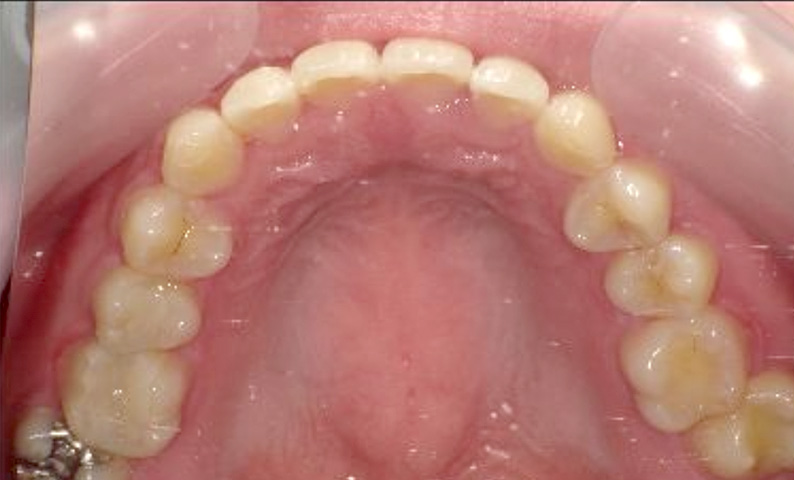

症例_009 上顎だけの部分矯正

治療期間:7ヶ月金額:24万円+税女性すきっ歯上の前歯だけ